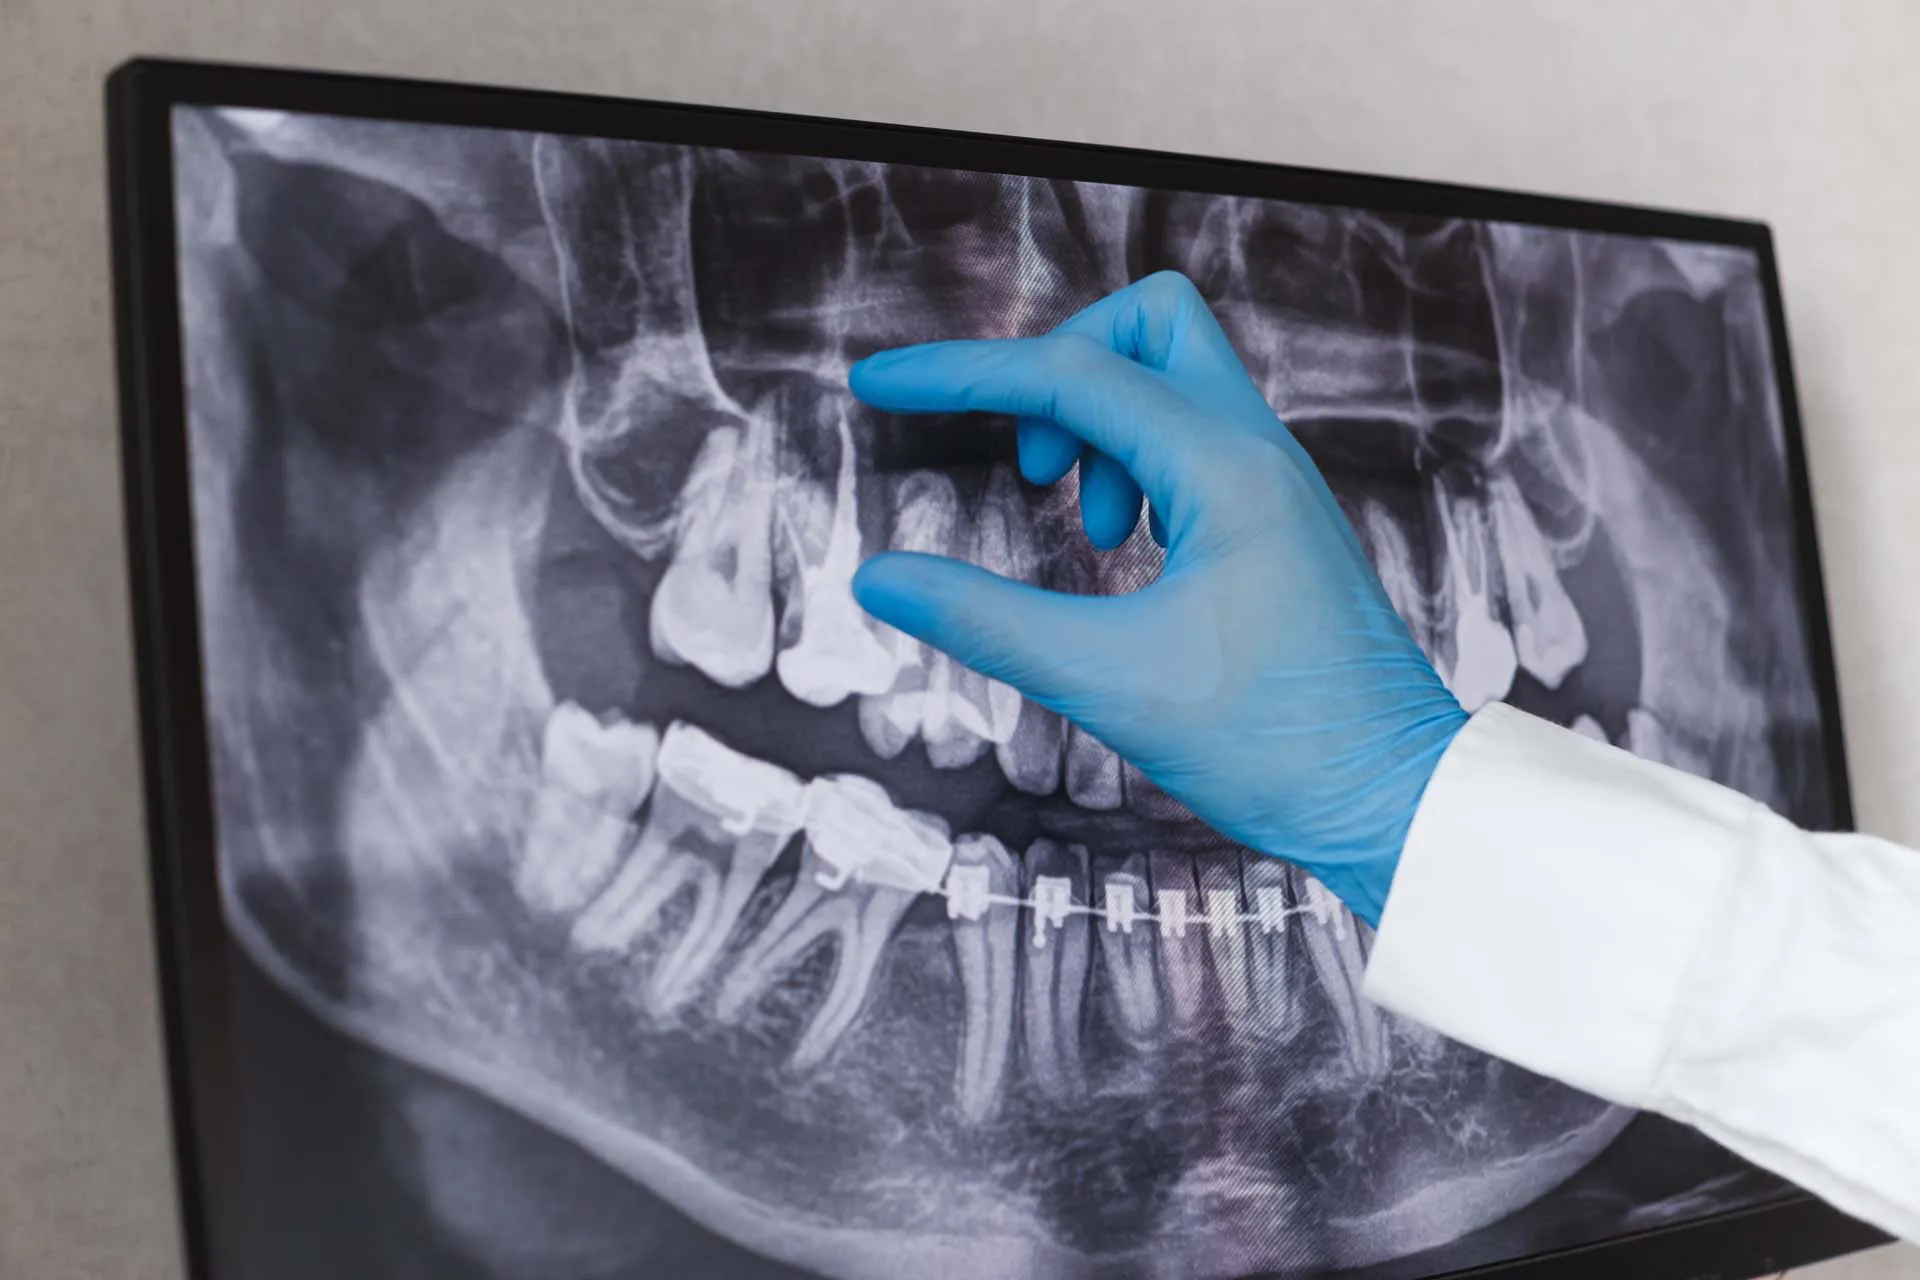

Panoramic X-Rays

Our panoramic X-ray system captures your entire mouth in one image — including your teeth, jaw, sinuses, and surrounding bone.

It’s a simple, non-invasive way to identify potential issues like impacted teeth, bone loss, or joint problems before they progress.